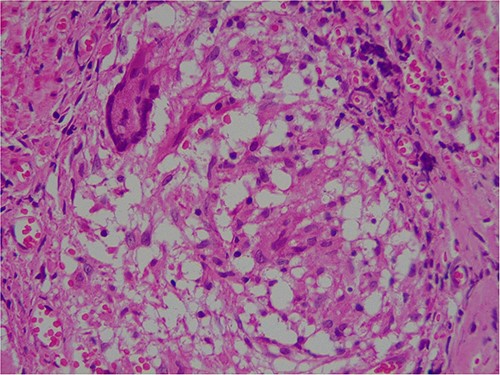

Intra-operatively, adhesiolysis of dense bowel and omental adhesions were performed. About 3.5-cm appendicular stump was resected (Fig. 3). Micro-nodular peritoneal nodules were noted and resected (Fig. 4). The specimens were sent for a histo-pathology examination. The postoperative period was uneventful with symptomatic relief. The biopsy of the gross specimen of stump appendix described a single white to grey brown soft tissue measuring 3 cm × 2 cm × 0.8 cm with a congested outer surface. The appendicular wall was 0.3 cm thick while the peritoneal nodule was a 2.5 cm × 0.8 cm × 0.5 cm single grey white to yellow soft tissue. Microscopic report of the appendix revealed multiple granuloma composed of epithelioid cells, macrophages, lymphocytes and multinucleated giant cells (Fig. 5). Caseation necrosis was seen in focal areas and with transmural mixed inflammatory cell infiltrate (Fig. 6). The peritoneal nodule showed fatty tissue with infiltration of lymphocytes, plasma cells and neutrophils microscopically.